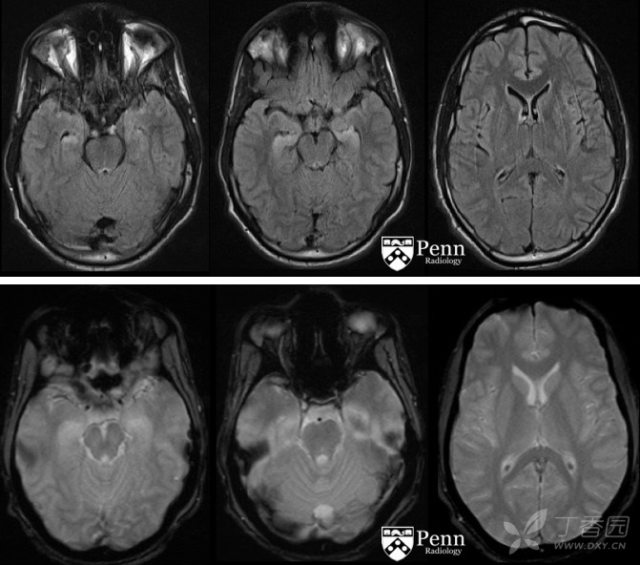

为了明确诊断,对患者进行了头颅 MRI 检查。颅脑轴位 T2-FLAIR、DWI、ADC 及 GRE MR 图像如下:

颅脑 MRI 显示双侧海马可见对称性 FLAIR 高信号及扩散受限。未见明显出血征象、占位效应或脑积水征象。未见明显特异性征象,可能是由于近期癫痫导致的。尽管缺氧缺血性脑病也可累及海马,但脑实质中无足够的证据支持缺氧缺血性脑病。

大脑不同的区域都可受累,包括海马(最为常见,约为 50% 病例可见)、丘脑(多见于丘脑后结节区域)、基底节、大脑皮层、皮层下白质和胼胝体。

MRI 上,常见表现为在受累区域出现 T2/FLAIR 异常高信号,通常这些表现是可逆的。

在受累区域也有可能出现 DWI 高信号,有时合并 ADC 低信号,这多提示为永久性损伤,有时尽管也是可逆的。

约有 50% 的病例病变是双侧的。